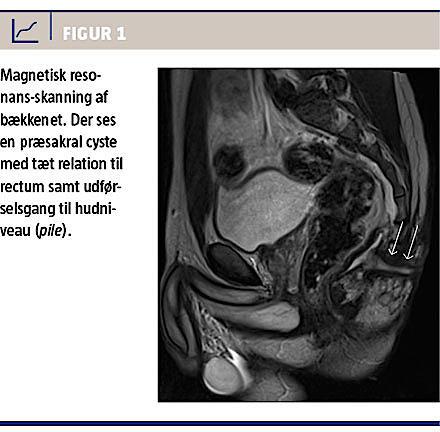

Der blev suppleret med transrektal UL-skanning og fornyet MR-skanning samt revurdering af den foreliggende radiologi, der samlet blev tolket som en inficeret kongenit præsakral cyste, som befandt sig klos på rectum (Figur 1). Cysten og fistelforløbet blev excideret in toto med Kraskes laterosakrale adgang. Såret helede, og et histologisvar fastslog, at det drejede sig om en epitelial inklusionscyste med fistel samt akut og kronisk inflammation.